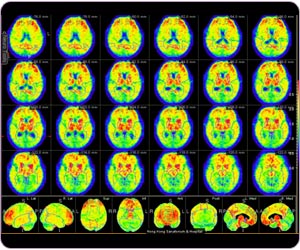

11C 標記PIB 正電子掃描腦部:病人在post cingulate gyrus, frontal lobe, precunes, parietal lobe, temporal lobe區域都呈現澱粉斑塊,診斷為阿耳滋海默氏病。

阿耳滋海默氏病 (11C標記PIB正電子掃描腦部)

11C標記PIB腦部正電子掃描:基於區域的定量分析